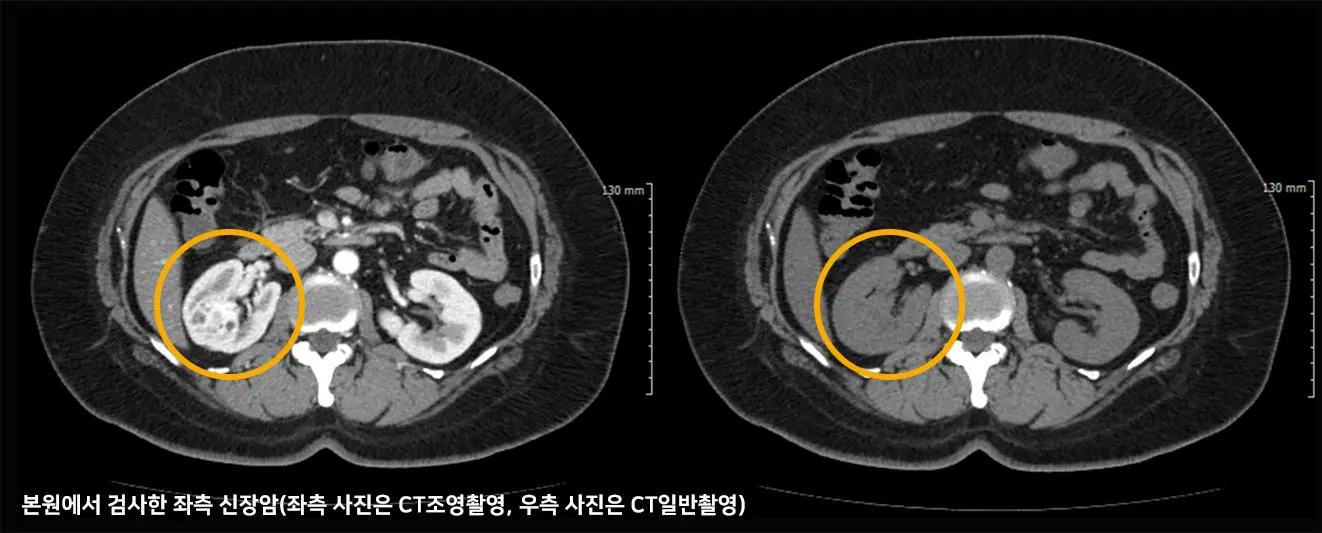

신장암

신장암(kidney cancer)은 신장에 발생하는 악성 종양을 의미하며, 신장의 세포들이 비정상적으로 증식하여 암을 형성합니다. 신장암은 비교적 조기에 발견되면 치료가 가능하지만, 진행된 경우에는 전이 가능성도 높아집니다.

• 신세포암

신세포암(Renal Cell Carcinoma, RCC)은 가장 흔한 신장암으로(80% 이상), 신장의 여과 기능을 담당하는 세뇨관에서 발생합니다.

• 진단

초음파, CT, MRI 등의 영상의학검사로 신장의 크기와 구조를 확인하고, 종양의 위치 및 전이 여부를 파악하며, 소변검사, 조직검사, 혈액검사 등을 통해 기능 및 타 장기와의 관계, 전이 여부 등을 파악하게 됩니다.